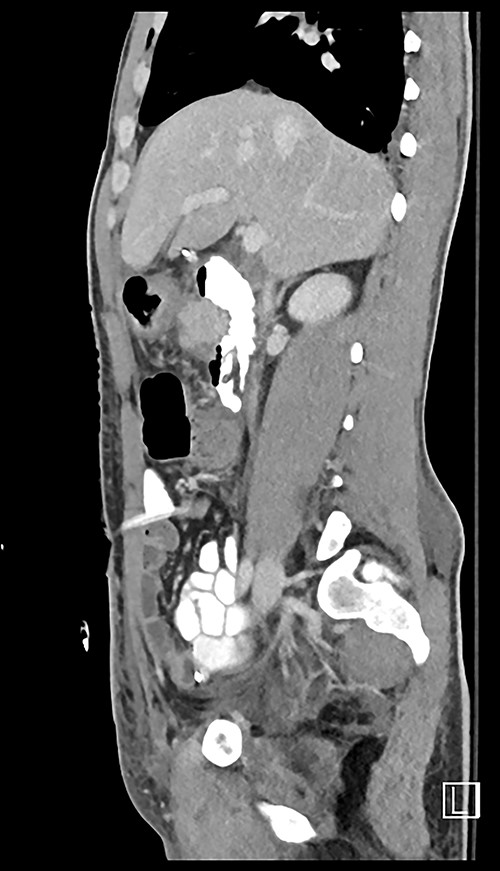

Here, we report a case of a 21-year-old man who was admitted to our hospital following a motor vehicle collision where he was a pedestrian, hit by a car and pushed against the bumper of another car. Upon arrival to the hospital, he was conscious and oriented, with normal vital signs. Abdominal examination revealed ecchymosis over the epigastric area with tenderness, however, no distention was noticed. Focused assessment with sonography for trauma result was positive in the right upper quadrant. His initial blood test results revealed a white blood cell (WBC) count of 26.5 × 109 cells/l and a hemoglobin level of 150 g/l. His serum amylase and lactic acid levels were 92 U/l and 4.53 mmol/l, respectively. His base deficit was 4.3. He underwent abdominal computed tomography (CT) with oral contrast, which showed query duodenal and possible pancreatic transection with active arterial extravasation (Figs 1–3). In addition, CT revealed a comminuted right intertrochanteric femoral fracture without associated vascular injury.

Despite its limitations in distinguishing between duodenal hematoma and duodenal perforation, CT with intravenous and intraluminal contrast remains the gold standard diagnostic test in stable patients with blunt abdominal trauma [1]. In the reported case, CT revealed duodenal and possible pancreatic transection with active arterial extravasation.